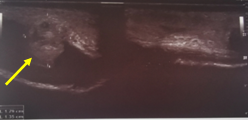

A 38 years old male patient presented to the hospital after hearing popping sound followed by asudden detumescence while having intercourse along with a profuse urethral bleeding, with no swelling or deformity of penis as shown in Figures 1&2. Local penile examination was unremarkable therefore,it was a bit misleading. Urethral catheter was inserted gently and carefully which drained clear urine andurethral injury was suspected. Patient was resuscitated and started on broad spectrum antibiotics as per the hospital`s protocol subsequently the patient had a considerableperiurethral bleeding that raised the suspicion of an additional underlying pathology; beyond the urethral injury. Ascending andmicturatingcystourethrogramin Figure 3 confirmed the presence of a tear in the tunica albuginea extending to the urethral lumen and draining the blood from the corpora cavernosa directly into the urethra, it did also show a normal filling of the anterior urethra with irregular extraurethral extravasation and finally a penile duplex ultrasound scan in Figure 4 confirmed the presence of multiple subtunical and bilateral extracorporeal small organized hematoma. Although the physical findings were not suggestive of a penile fracture, exploration was offered and advised to the patient in the view of the finding but unfortunately the patient refused to undergo exploration after settling of the urethral bleeding and he was fully and formally informed about the possibility of the associated risks mainly erectile dysfunction. The patient was self-discharged and represented 3 month later, with moderate degree of erectile dysfunction and examination revealed a 3 cm fibrotic plaque on ventral aspect of left corporeal body.

Figures 1&2 Showing nearly normal penile shaft.

Figure 4 Duplex US showing presence of extracorporeal small organized hematoma (yellow arrow).